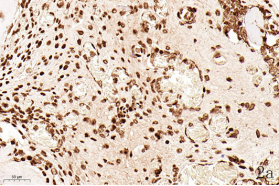

NDN(Necdin)屬于黑色素瘤抗原(MAGE)家族,由60多個基因構(gòu)成共享高度保守的MAGE同源結(jié)構(gòu)域(MHD)[6,7]。最近幾年的研究提出NDN是一種新的抑癌基因,其在卵巢癌[8]、乳腺癌[9]和黑色素瘤[10]等的組織和細胞系中低表達,過表達NDN可以抑制其生長,但NDN在骨肉瘤中的作用及機制尚不清楚。為探討NDN在骨肉瘤中的作用及途徑,我們收集了骨肉瘤患者的石蠟標本以及臨床信息,對其進行了免疫組化檢測及生存分析。通過對骨組織和骨肉瘤HE染色發(fā)現(xiàn),骨組織組,骨密質(zhì)呈板層狀,陷窩中可見骨細胞呈梭形排列( 圖1 a 1b) ;骨肉瘤組,瘤細胞呈多角形,核大深染,核分裂多見,瘤細胞呈車輻狀排列,瘤細胞間可見少量腫瘤性骨質(zhì)形成(圖1c1d)。同時通過免疫組化發(fā)現(xiàn),NDN表達主要位于細胞的胞核中。NDN在骨肉瘤組織中的表達率為29.4%(15/51)(圖1c1d),明顯低于瘤旁骨組織陽性表達率80%(8/10)(圖1a1b)。